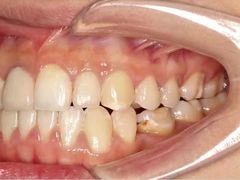

• -联合口腔(西环诊所)

在丽江古城跳舞的炒鸡蛋 | 21-05-08

报错